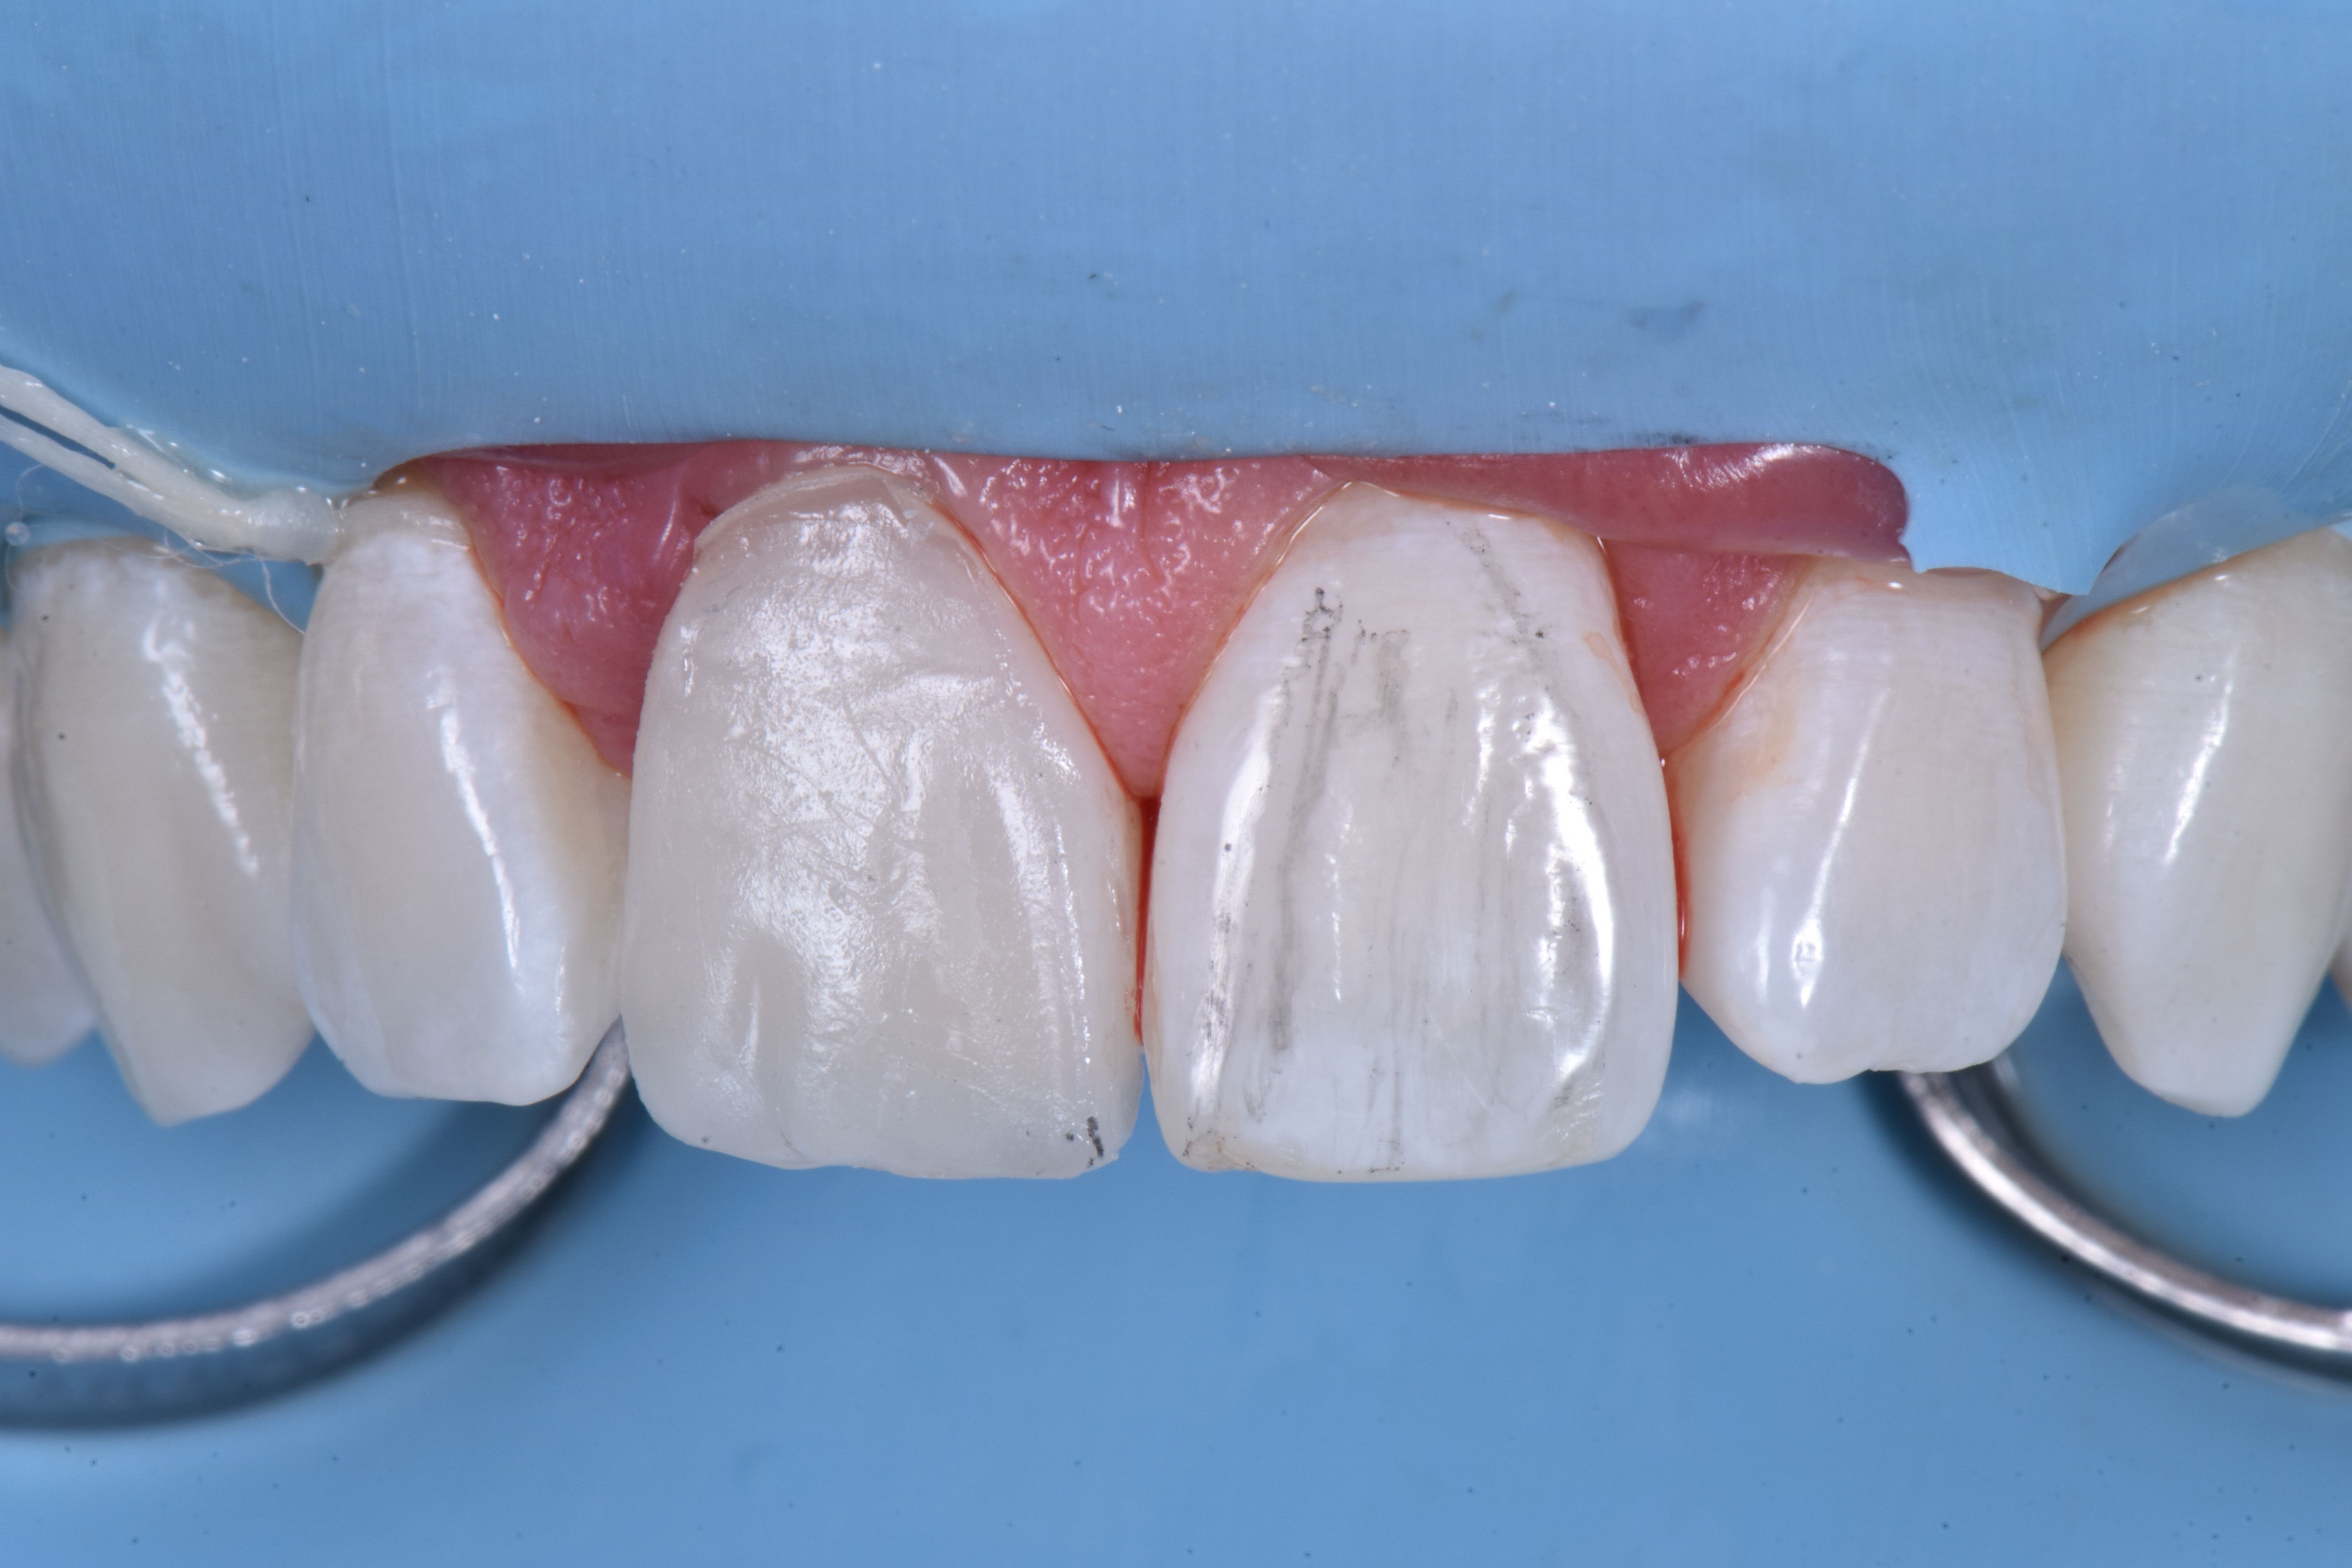

Przedsionkowy profil wyłaniania odtworzono kompozytem w odcieniu szkliwa (ESTELITE ASTERIA WE firmy TOKUYAMA DENTAL) (ryc. 7).

Z użyciem silikonowego indeksu diagnostycznego wykonanego na podstawie modelu wax-upu rekonstrukcję ściany od strony podniebiennej kompozytem w odcieniu szkliwa (ESTELITE ASTERIA WE firmy TOKUYAMA DENTAL) (ryc. 8).

Następnie zrekonstruowano anatomię zębiny poprzez odtworzenie mamelonów przy użyciu opakerowego odcienia kompozytu do zębiny (ESTELITE SIGMA QUICK OA2 firmy TOKUYAMA DENTAL); odcień ten miał również zasadnicze znaczenie dla skorygowania odcienia przebarwionej korony (ryc. 9).

Jasnoniebieskie i białe odcienie (ESTELITE COLOR firmy TOKUYAMA DENTAL) zastosowano w celu odtworzenia opalescencji w obszarze siecznym (ryc. 10).

Odbudowę uzupełniono poprzez zastosowanie odcienia szkliwnego (ESTELITE ASTERIA WE firmy TOKUYAMA DENTAL) w postaci jednej warstwy. Powierzchnię przedsionkową wymodelowano i skontrolowano w każdym wymiarze, aby jak najmniej trzeba było ostatecznie korygować. Następnie spolimeryzowano w ciągu 20 sekund, a potem przez 40 sekund od strony przedsionkowej i podniebiennej po pokryciu żelem glicerynowym w celu uniknięcia powstania warstwy inhibicji tlenowej kompozytu (ryc. 11).